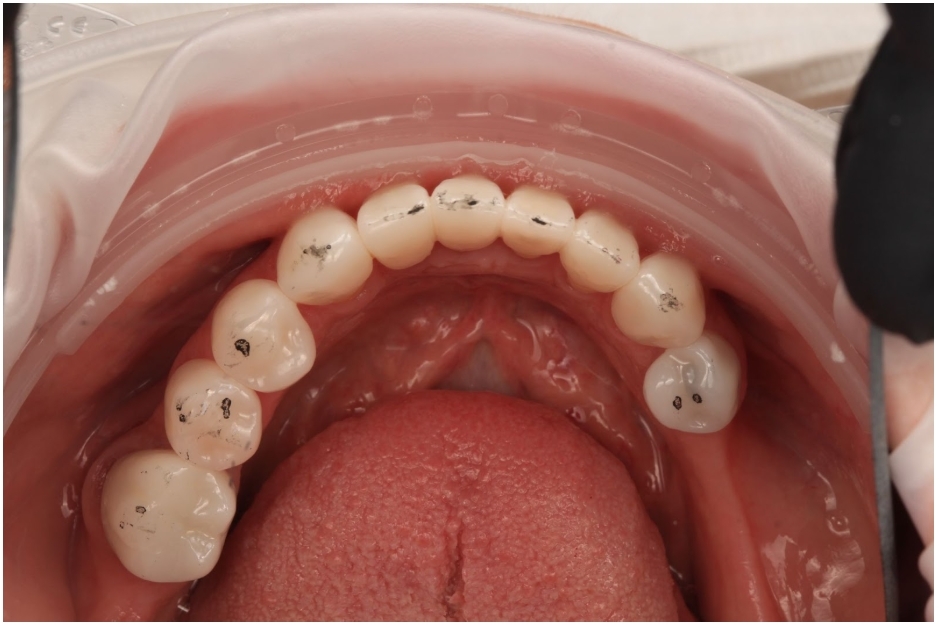

Articulating paper is the most universally used tool in clinical dentistry. Every dental school teaches it. Every clinic stocks it. The workflow is ingrained: have the patient tap, examine the marks, and adjust whatever looks heavy.

The traditional teaching — passed down through occlusion textbooks for decades — is that larger, darker articulating paper marks indicate heavier occlusal force, and smaller, lighter marks indicate lighter force. This forms the basis for how most clinicians decide which contacts to adjust.

To put it plainly: the marks are overwhelmingly shaped by tooth anatomy and contact area geometry, not by how much force is at that contact. When we look at a big dark mark and decide it’s a “high spot,” we’re reading the wrong variable.

So what do we have? A material that doesn’t accurately record the native occlusion. That generates false positive contacts from its own thickness. That produces marks whose size is unrelated to force. And that clinicians — including specialists — cannot reliably interpret.

I still use articulating paper every day. It has a role. But I never adjust based on only the markings I see. I have to confirm those markings — and that is done with shimstock.

Articulating paper can supplement shimstock by providing a visual map of approximate contact location. But shimstock is what confirms whether a contact is real. That’s what I need verified before I pick up a handpiece.

Before adjusting any occlusion. Don’t adjust based on what a paper mark looks like. Verify with shimstock which contacts are real first, then use the paper marks as a map to locate them.